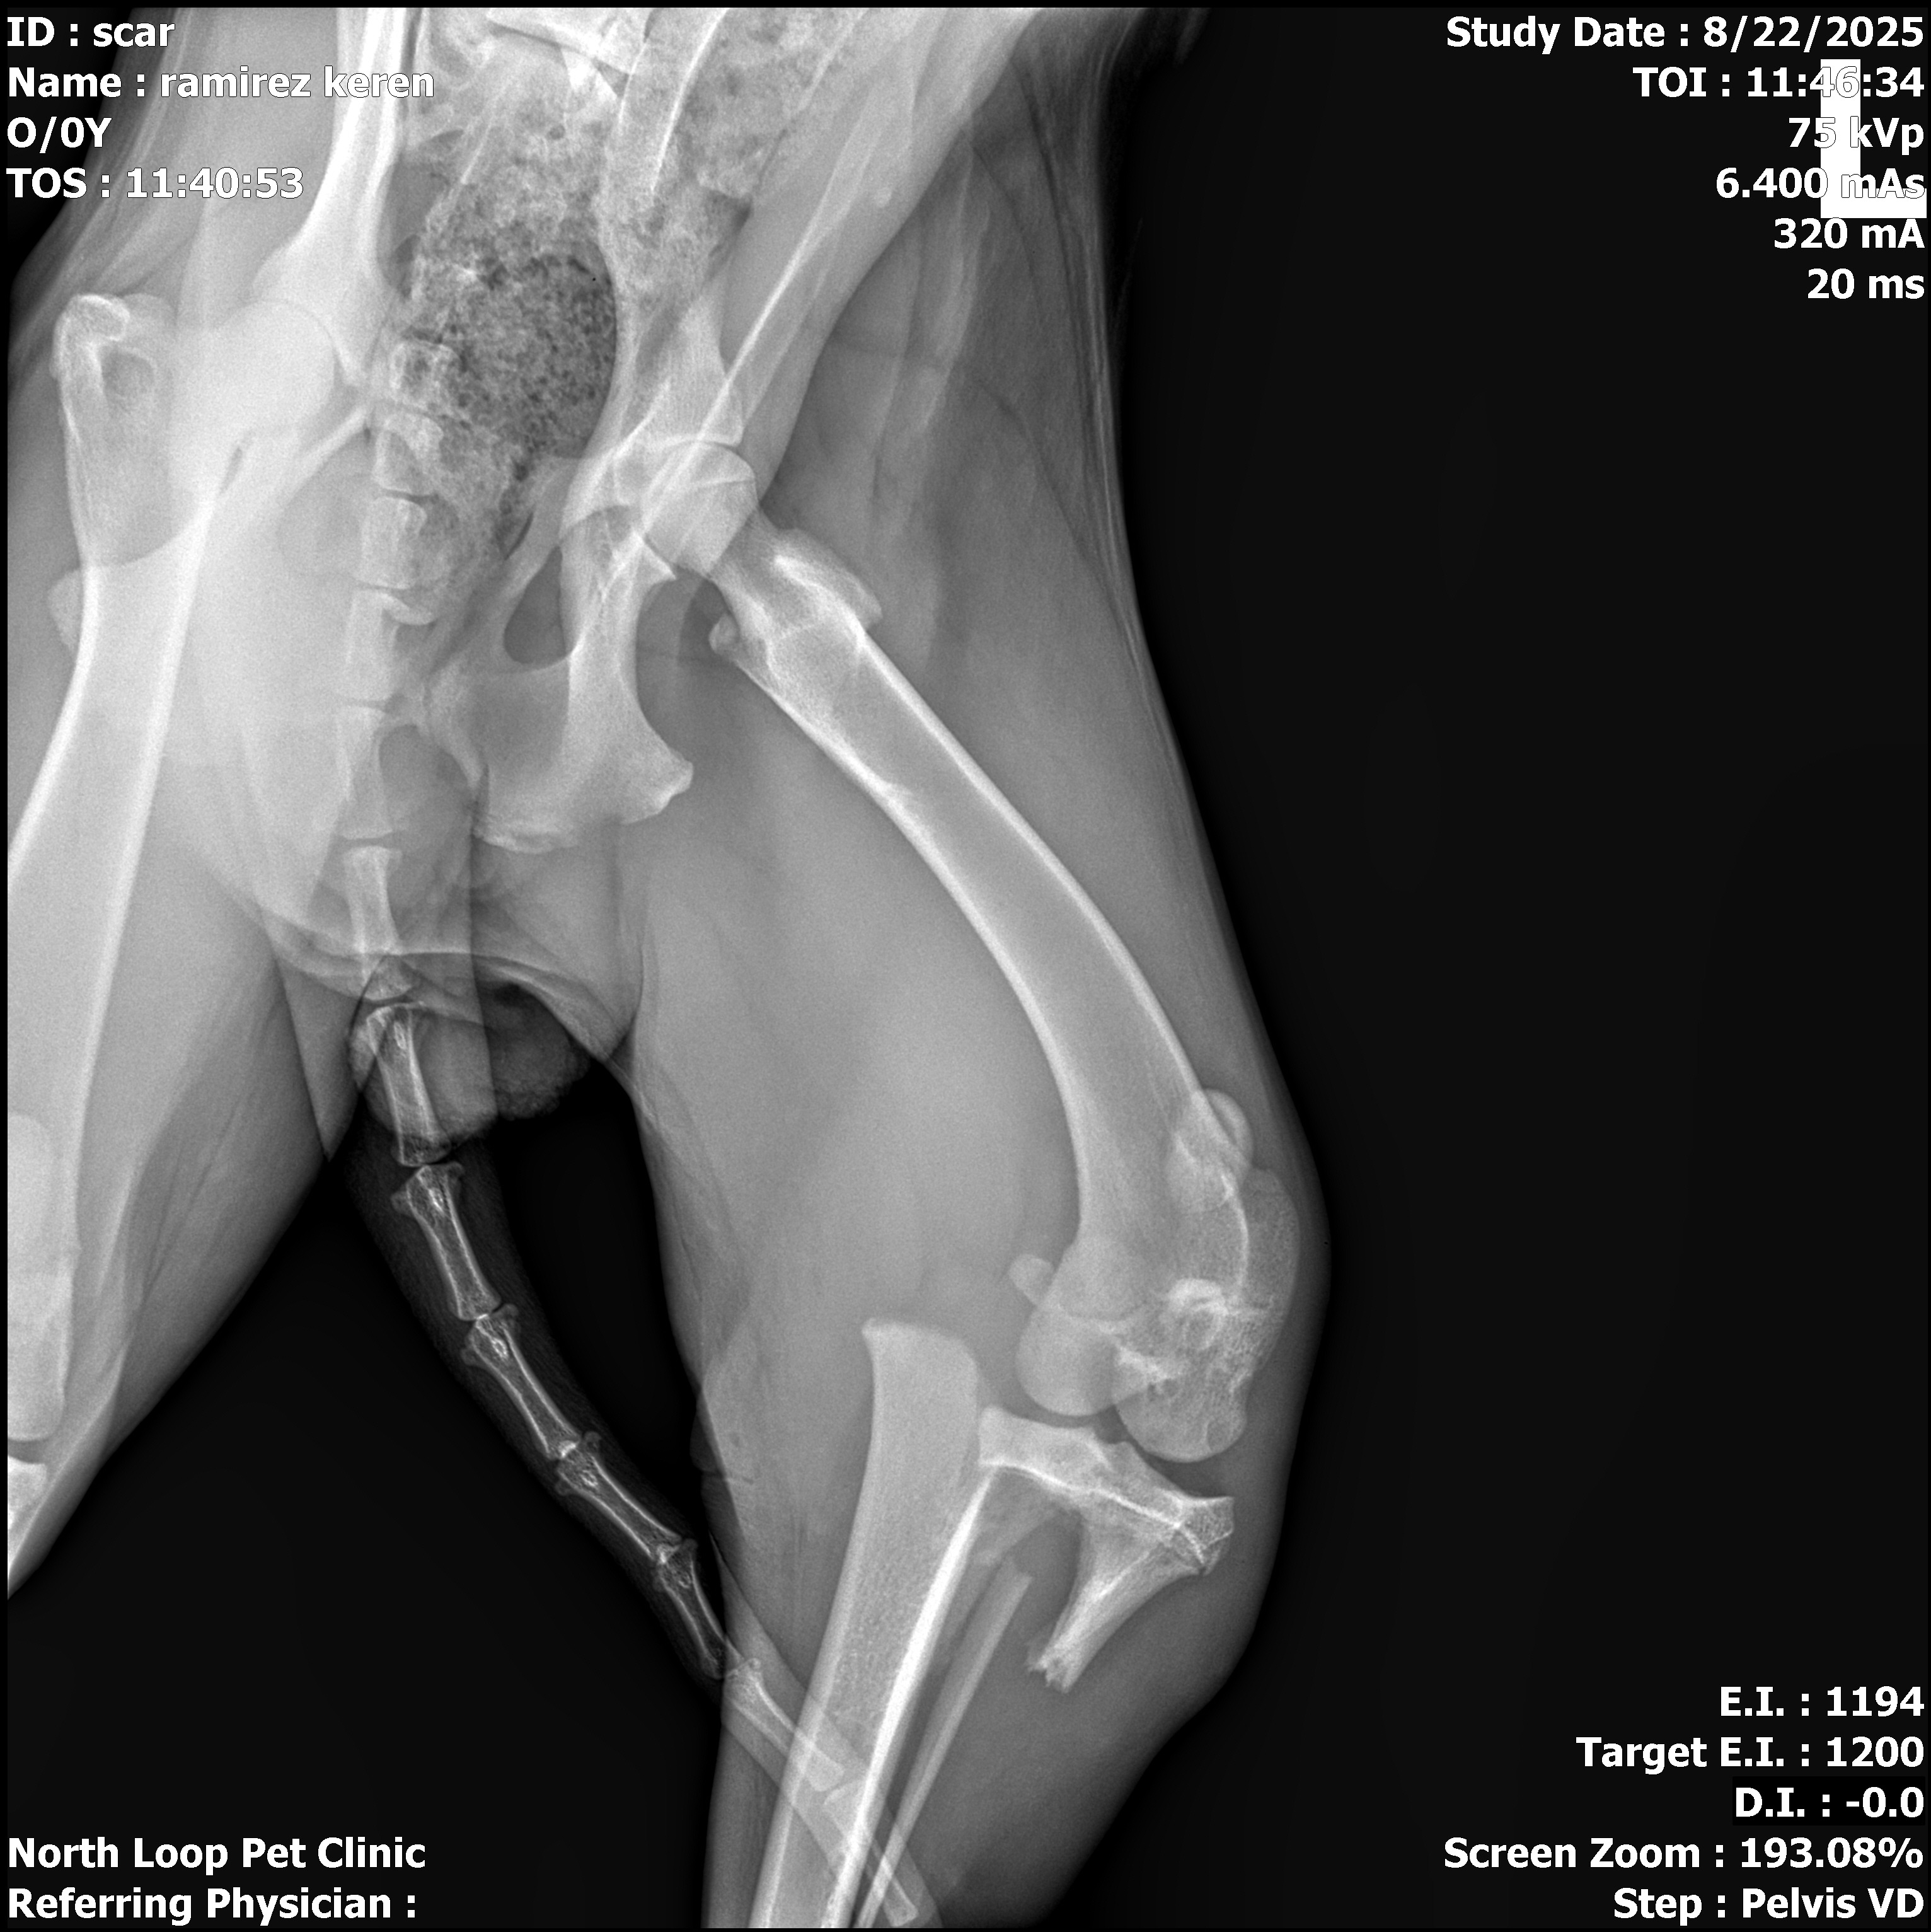

Hello my name is Keren Ramirez and Im from Magnolia Tx. I hope you can help me raise money for our dog Scar ( basically my Daughter's dog) who has a fractured his leg on the fibula. On Friday,15th 2025, a truck didn't see Scar passing by the street and ran over him, they didn't even bother to stop and look if Scar was okay. We went to the vet and has to get surgery on his leg, I have try so many places and see if they can help but he needs to go to a specialist orthopedic wich they charge a lot. Please if you can help out Scar have his surgery he is a lovely dog and we hope he gets the attention he needs. I know he will appreciate your help as we do. One dollar will make a difference. Thank you and God bless everyone.I